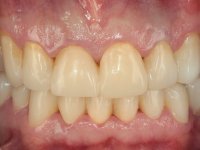

Foi proposto ao paciente fazer uma reabilitação total com infraestruturas em zircónia revestidas a cerâmica. No maxilar superior, seriam realizadas 6 coroas (1.3/1.2/1.1/2.1/2.2/2.3), uma ponte de 3 elementos (1.4/1.5/1.6) e uma ponte de 4 elementos (2.4/2.5/2.6 e 2.7). No maxilar inferior, foram propostas 7 coroas (4.3/4.2/4.1/3.1/3.2/3.5 /3.6) e duas pontes (4.4//4.5/4.6) e (3.3/3.4#/3.4).O objetivo seria subir a D.V.O., descruzar a mordida do lado direito, eliminar as infiltrações e as exposições radiculares e reabilitar o paciente com estruturas protéticas com aspeto mais natural.

Avaliada a situação inicial em conjunto com o médico dentista, foi considerado prioritário alterar a forma dos dentes, subir 1.5mm a D.V.O. e descruzar a mordida do 1º Quadrante. Na confeção da ponte provisória superior de acrílico com reforço metálico foram já ensaiadas essas alterações. Optamos por um monobloco de 13 dentes com o intuito de manter a estabilidade posicional dos dentes re- preparados. Após remoção das coroas e pontes antigas foi feita a re-preparação dentária. A ponte provisória foi rebasada em boca, primeiro com acrílico auto-polimerizável e depois com resina composta. Após 4 semanas de integração da ponte provisória superior foi confecionada a ponte provisória inferior, corrigindo-se finalmente as discrepâncias existentes no plano oclusal. As impressões foram realizadas com a técnica de dupla mistura, com dupla mistura. Simultaneamente foram feitos os registos da relação inter-maxilar e da relação do maxilar superior com a base do crânio, utilizando o arco facial. Montados os modelos de trabalho em articulador semi-ajustável, foram confecionadas as peças próteticas, utilizando tecnologia CAD-CAM para a realização das infra-estruturas em zircónia. A colocação da cerâmica foi feita procurando que a forma dos dentes reproduzisse uma forma anatómica natural. A tonalidade foi condicionada pela vontade do paciente. Foi feita uma prova com a cerâmica em “biscuit” para verificação técnica e validação estética. Após aprovação pelo paciente o trabalho foi finalizado e colocado em boca.